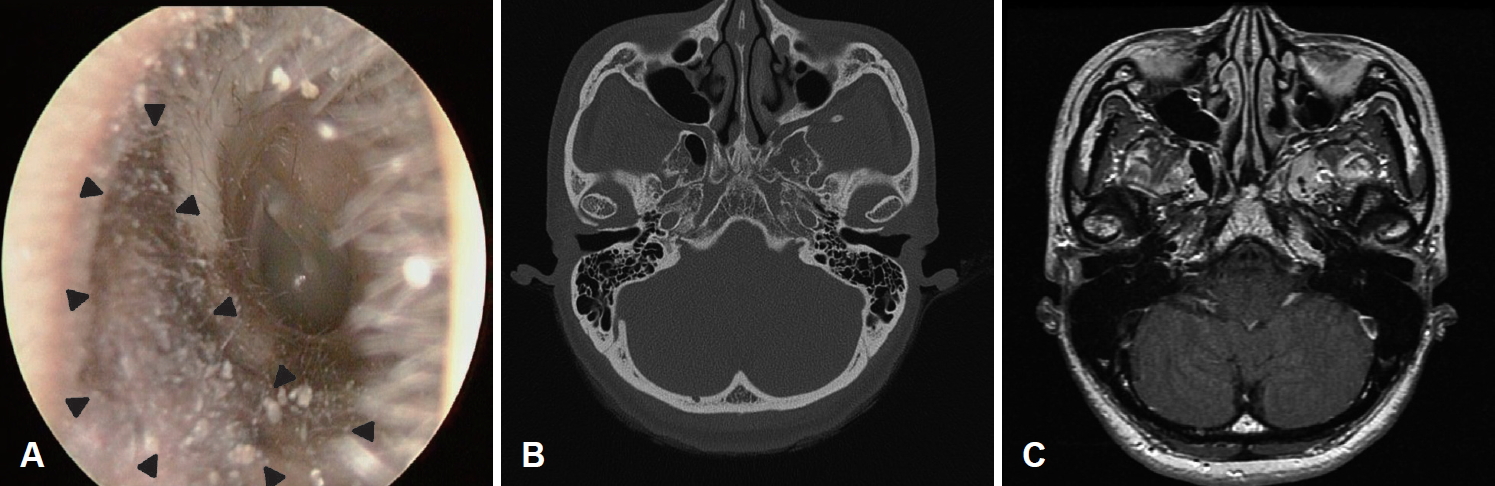

내원 시 이학적 검사에서 양측 이개와 고막은 정상 소견이었으나, 좌측 외이도 연골부 전하벽에 경계가 불명확한 가피와 인설로 덮인 갈색의 과각화성 병변이 관찰되었다(Fig. 1A). 정확한 진단을 위해서 외래에서 국소마취하에 생검을 시행하였고, 조직검사상 편평세포상피내암종으로 진단되어, 다른 날 전신마취하에 국소 광범위 절제술 및 피부이식을 계획하였다. 수술 전 시행한 측두골 전산화단층촬영 및 측두골 자기공명영상촬영상에서는 병변이 명확하게 구분되지 않았고 병변 주위로도 특이사항은 관찰되지 않았다(Fig. 1B and C). 수술은 경외이도로 접근하여 병변 주위에 5 mm 절제연을 두고 절개를 가하였고, 깊이는 연골막 윗쪽으로 박리하여 병변 부위를 완전 절제하였다. 병변 제거 후 결손 부위를 재건하기 위해 좌측 후이개 피부에서 2.0×1.0 cm 크기의 부분층 피부이식편(split thickness skin graft)을 채취하여 외이도의 결손 부위에 이식하였다. 절제 변연부에서 시행한 동결 절편검사는 음성이었고, 조직병리학적 검사에서 기질침범이 없으며 표피 전층에 걸쳐 비정형적인 편평상피세포로 이루어져 있는 편평세포상피내암종으로 최종 진단되었다(Fig. 2). 수술 후 환자는 이전에 호소하였던 외이도 이물감 및 이루 증상이 소실된 상태로 18개월째 재발 소견 없이 외래 추적 관찰 중에 있다(Fig. 3).